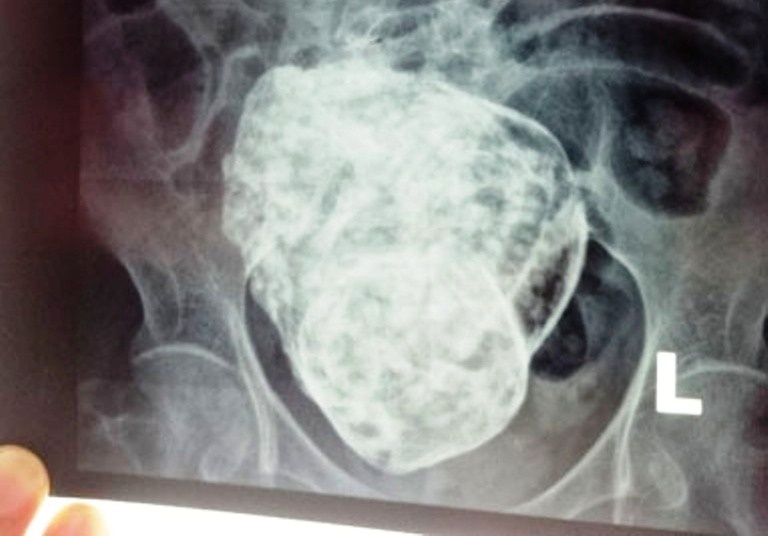

Ngày 31/3, bệnh viện Khánh Hòa sẽ cùng hội chẩn với bệnh viện Cam Ranh về trường hợp cụ bà mang thai đá hiếm gặp vừa được phát hiện.